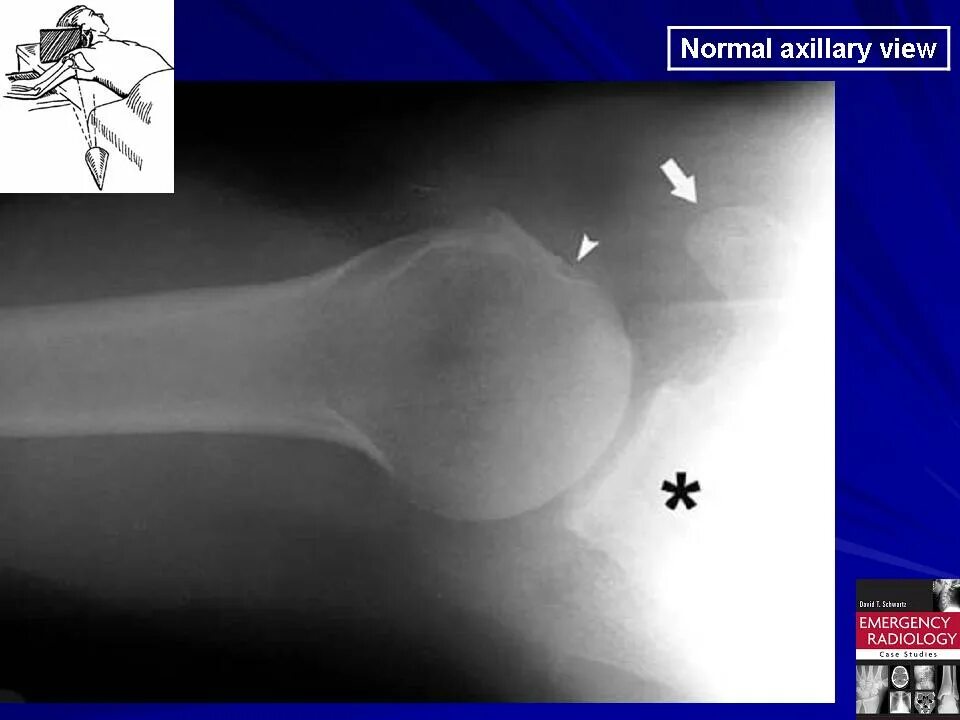

Нестабильность плечевого сустава мкб